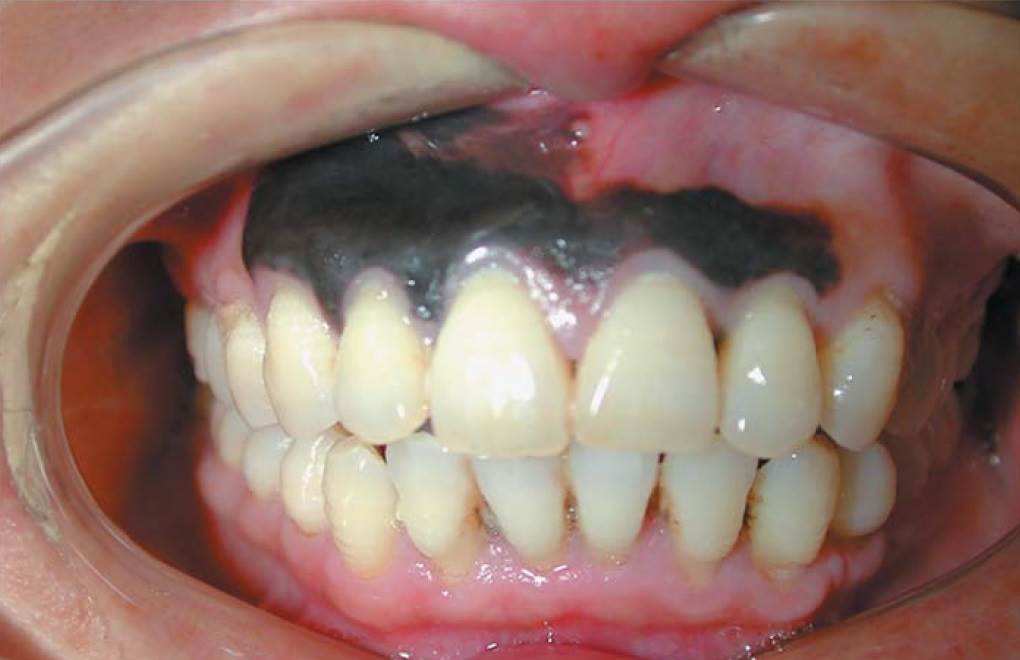

Gum disease black gums. Applying black tea bags all over the black gums or drinking will help to get rid of black gums. However over time it will start to damage the gums and underlying bone. Black gum disease or necrotizing periodontal disease however is an uncommon but serious form of gum disease that requires immediate treatment.

The discoloration which tends to be black in color is as a result of dead tissue or necrosis on the affected areas of the gum. What If Black Gums are Caused by Periodontal Disease. This inflammation could cause the gums to swell and bleed at first.

It can present as a black line on the gum around the teeth. Gum diseases often cause inflammation of the gum which is also called gingivitis. If your dark gums are caused by gum disease youll want to treat the disease either before or while youre correcting the color of your gums.

Gum diseases may also cause darkening of the gums. When the gums are receiving enough oxygen they are a nice bubble gum pink.